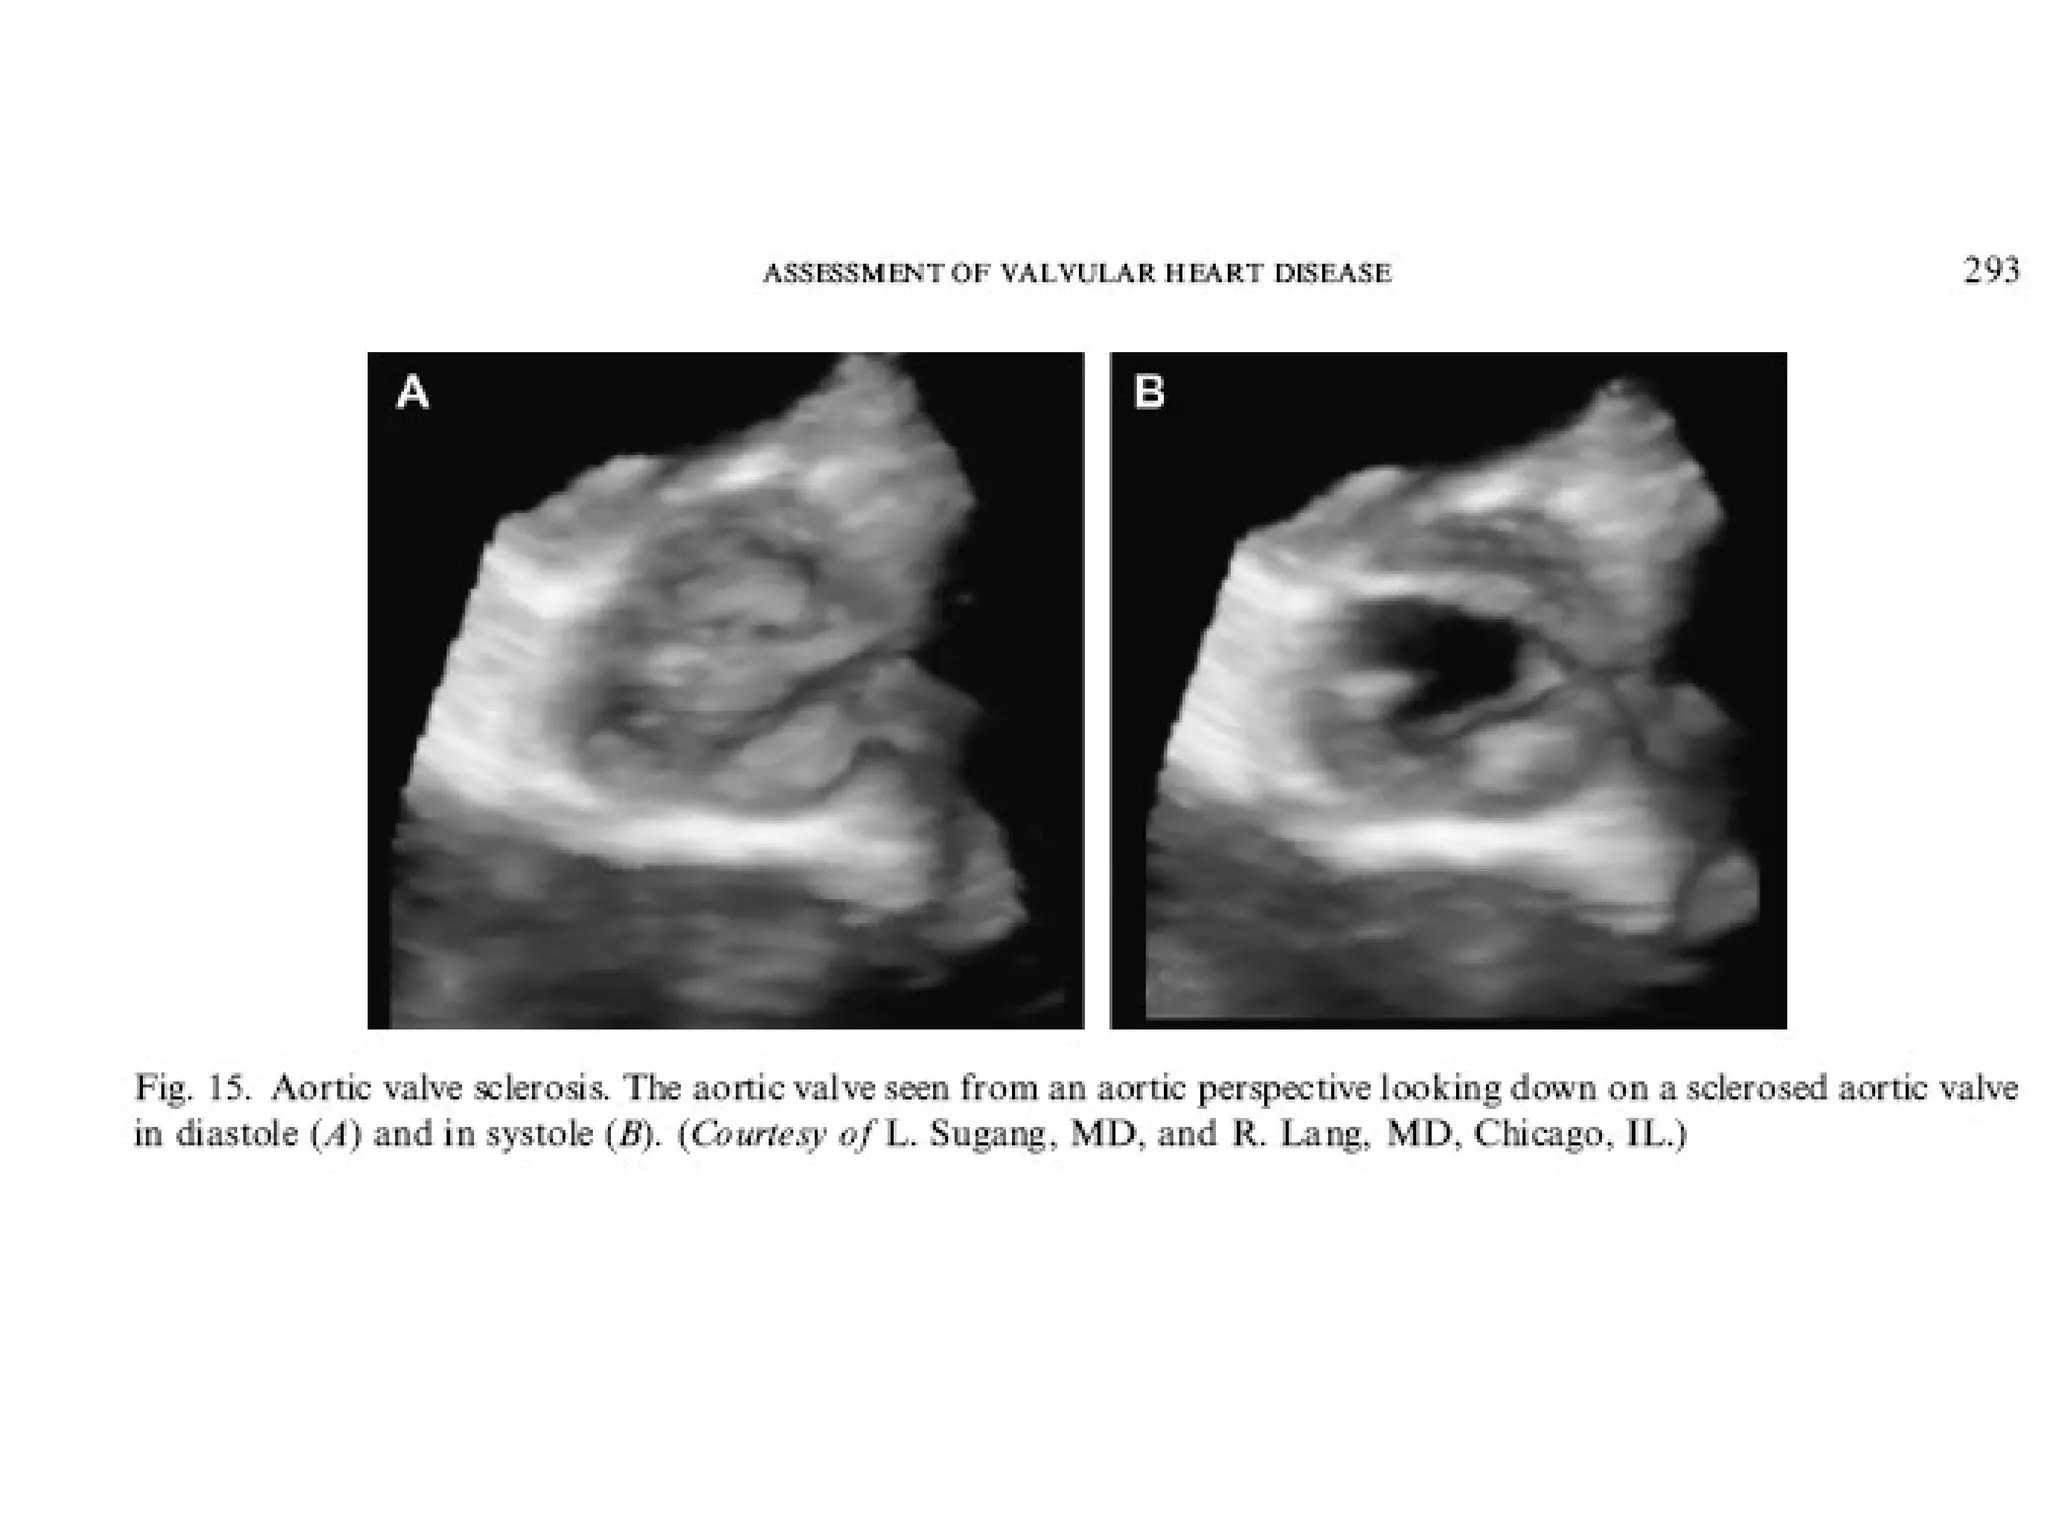

• 153.

M-mode at theAortic Valve Seen in aortic sclerosis Thickened, calcified aortic valve leaflet.